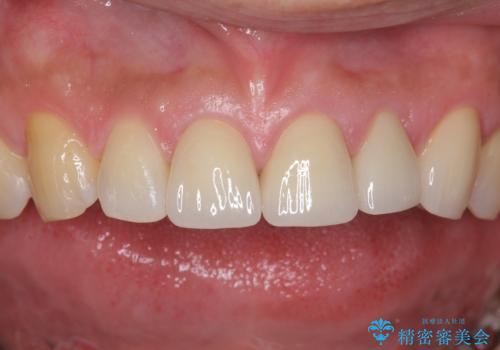

また、左上犬歯の詰め物は途中で脱離し、セラミックでの修復をご希望されたため、一緒に治療しました。

結果ナイトガードの使用によりぐらつきはだいぶ回復してきたため連結はしていません。

- 81.4万円 内訳:ジルコニアクラウン(スタンダード)11万円×4本 /精密根管治療 前歯、イニシャル 6万円×3本 /ファイバーコア 2万円×3本 /仮歯 1万円×3本/フラットタイプナイトガード 3万円費用は治療当時の料金となります

今後事故の影響でほかの歯の神経が死んでしまったり、状態が変化する可能性があるため経過観察が大事になってきます。